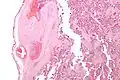

It can be diagnosed by histomorphologic examination of the placenta and is characterized by fetal vessel thrombosis and clustered fibrotic chorionic villi without blood vessels.

Very high mag.